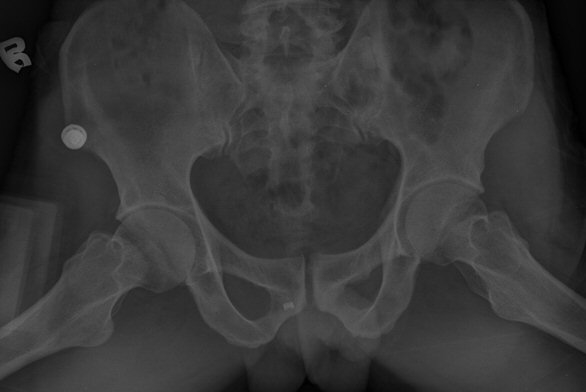

ŽÃËÀÚ¸¦ ¾ûµ¢ÀÌ °üÀý ¿ÜÃø Á¾´Ü¸é°Ë»ç ½Ã ÀüÇÏÀ屨(AIIS)¿¡¼­ ¼®È¸È­¼º À½¿µÀÌ °üÂûµÊ(»çÁø 2, 3).

ÃÊÁø ½Ã ½ÃÇàÇÑ ¹æ»ç¼± ÃÔ¿µ»ó ÀüÇÏÀ屨 ºÎÀ§¿¡¼­ ¼®È¸È­ À½¿µÀÌ °üÂûµÇ°í, 3ÁÖ ÈÄ ½ÃÇàÇÑ ÃÔ¿µ¿¡¼­

¼®È¸È­ À½¿µ ¼Ò½ÇÀÌ È®ÀεÊ.